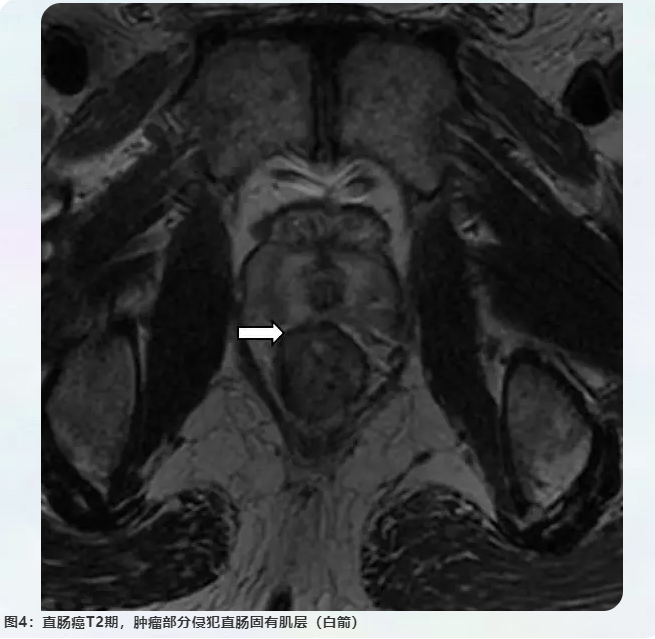

壹生资讯 结直肠癌规范化诊疗 影像篇 Mri精准诊断和评估直肠癌

壹生资讯 结直肠癌规范化诊疗 影像篇 Mri精准诊断和评估直肠癌